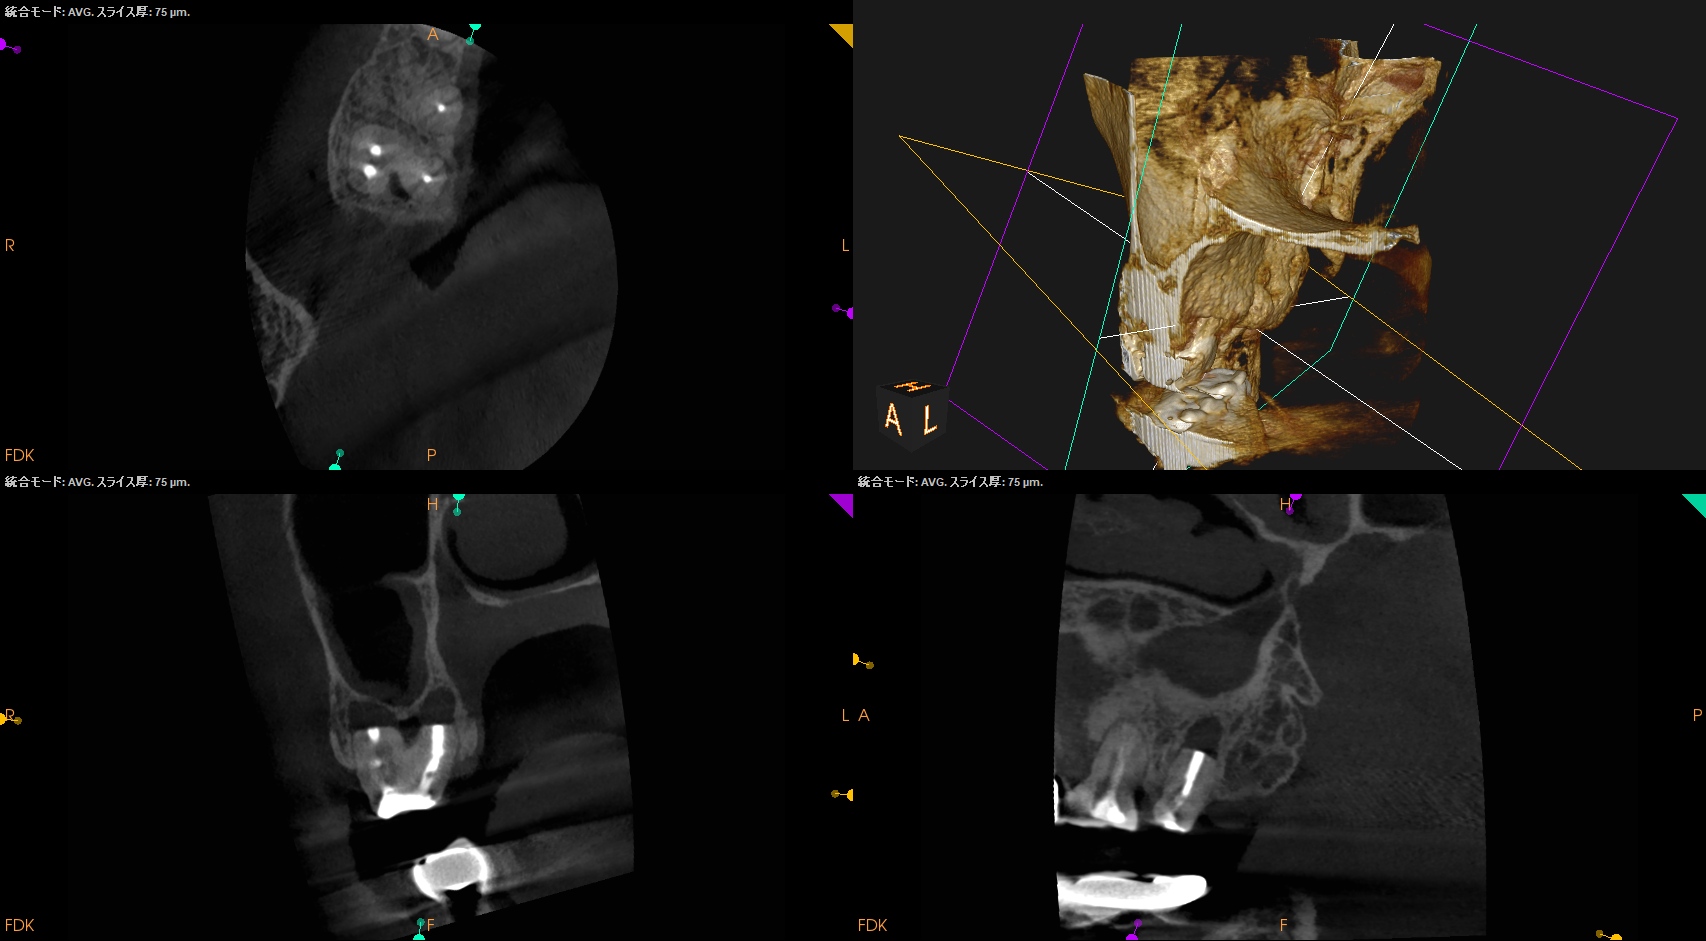

術後に口腔内PA, CBCTも撮影した。

MB

DB

P

ということで問題が客観的にないことがわかる。